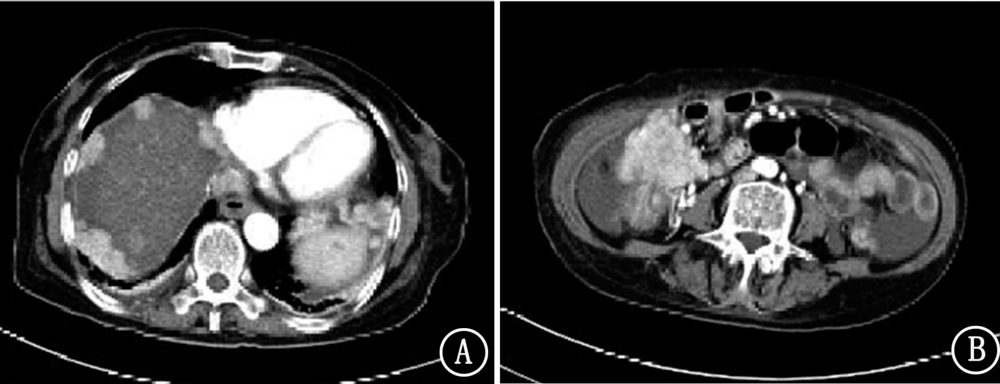

晚期胃癌目前无明确有效治疗手段,现报道1例安罗替尼治疗晚期胃癌病例,并对其临床疗效和安全性进行分析。